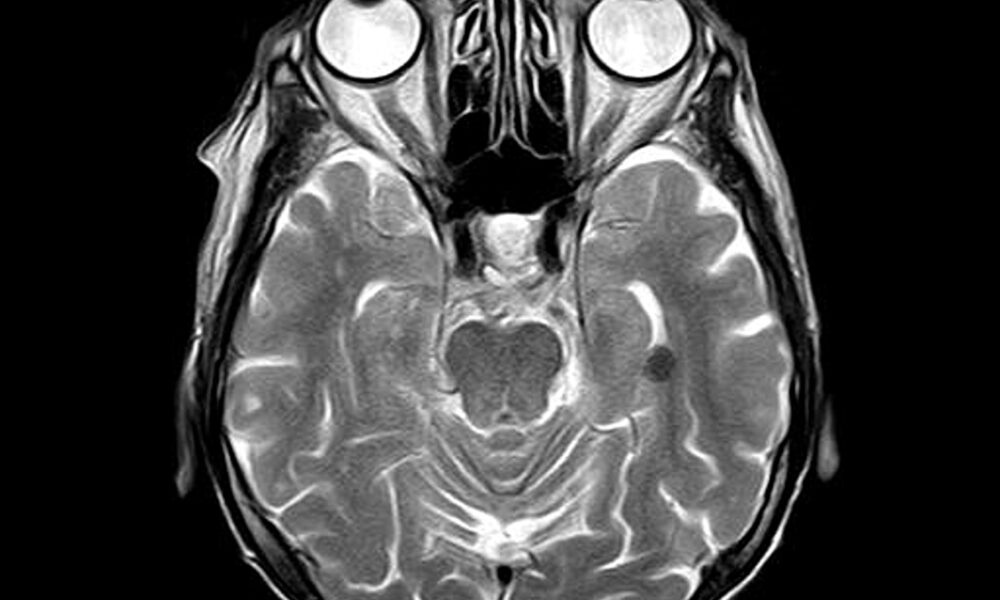

Scienziati in Corea del Sud hanno creato una nuova interfaccia neurale durevole in grado di misurare i segnali cerebrali direttamente all’interno del cervello stesso....